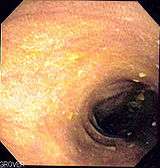

Melanosis coli

Melanosis coli, also pseudomelanosis coli, is a disorder of pigmentation of the wall of the colon, often identified at the time of colonoscopy. It is benign, and may have no significant correlation with disease. The brown pigment is lipofuscin in macrophages, not melanin.

However, other causes are identified, including an increase in colonic epithelial apoptosis.[3] Endoscopically, the mucosa may show a brownish discoloration in a moire pattern.